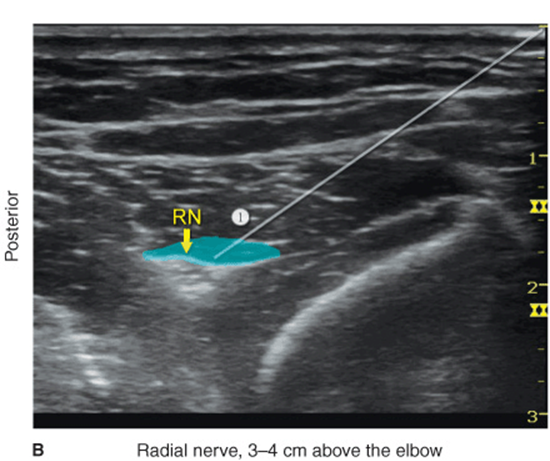

Radial Nerve

With the patient in the proper position, the skin is disinfected and the transducer positioned so as to identify the radial nerve. The needle is inserted in-plane, with the goal of traversing the biceps brachii muscle and placing the tip next to the radial nerve (Figure 33-6A). If nerve stimulation is used, a wrist or finger extension response should be elicited when the needle is in proximity to the nerve. After negative aspiration, 4–5 mL of local anesthetic is injected (Figure 33-6B). If the spread is inadequate, slight adjustments can be made and a further 2–3 mL of local anesthetic administered.

FIGURE 33-6. (A) Needle position to block the radial nerve (RN) at the elbow. BM - Brachialis Muscle, BrM - Brachioradialis muscle. (B) Local anesthetic (area shaded in blue) distribution to block the RN above the elbow. (1) Biceps brachii muscle.